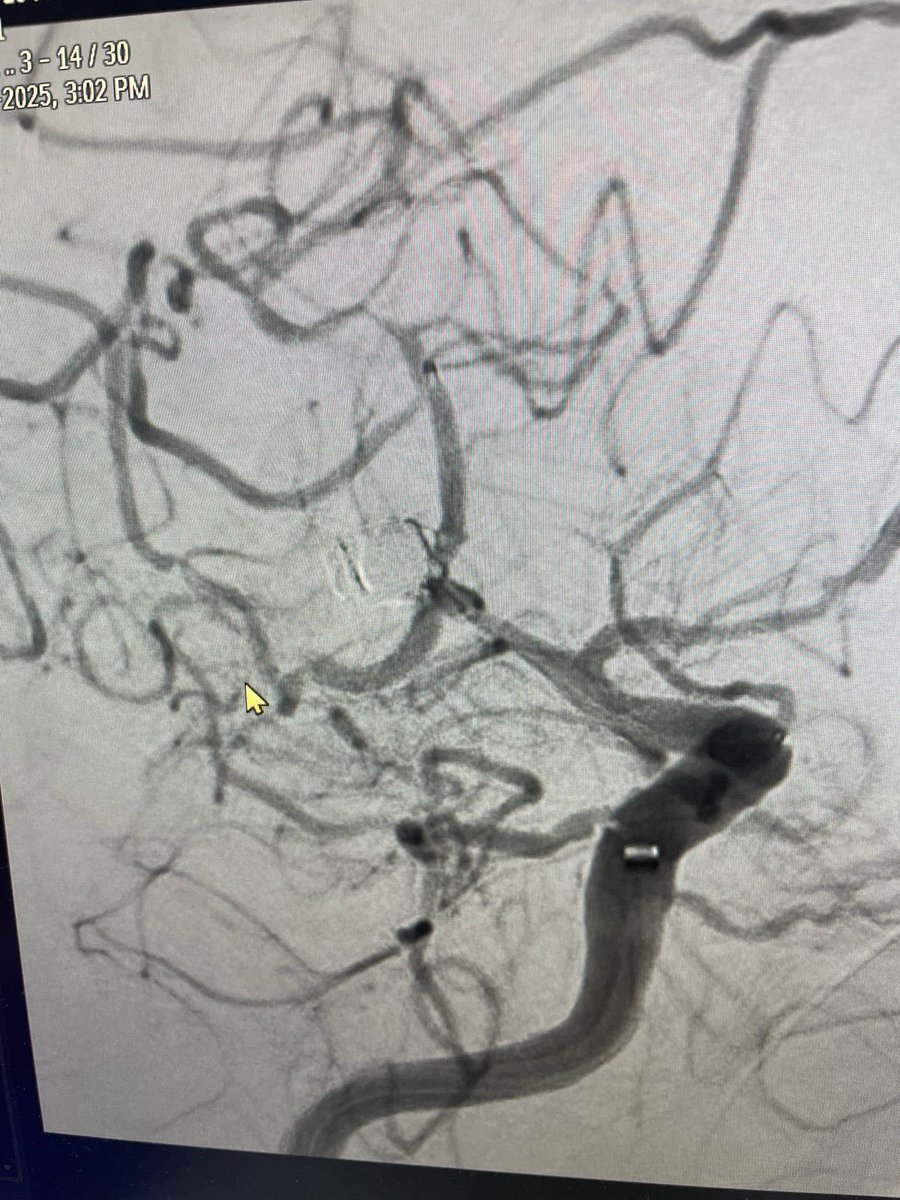

حالة من أصعب الحالات التي أجريتها لمسن ثمانيني يعاني من جلطة حادة أدت إلى شلل حاد في الجهة اليمنى من الجسم مع صعوبة في الإدراك والتحدث. القسطرة أكدت وجود تسلخ حاد في الشريان السباتي الأيسر وبحمد اللّٰه تم سحب الجلطات وإعادة التروية. بفضل اللّٰه المريض أصبح قادرًا على التحدث

حالة من أصعب الحالات التي أجريتها

لمسن ثمانيني يعاني من جلطة حادة أدت إلى شلل حاد في الجهة اليمنى من الجسم مع صعوبة في الإدراك والتحدث.

القسطرة أكدت وجود تسلخ حاد في الشريان السباتي الأيسر وبحمد اللّٰه تم سحب الجلطات وإعادة التروية.

بفضل اللّٰه المريض أصبح قادرًا على التحدث